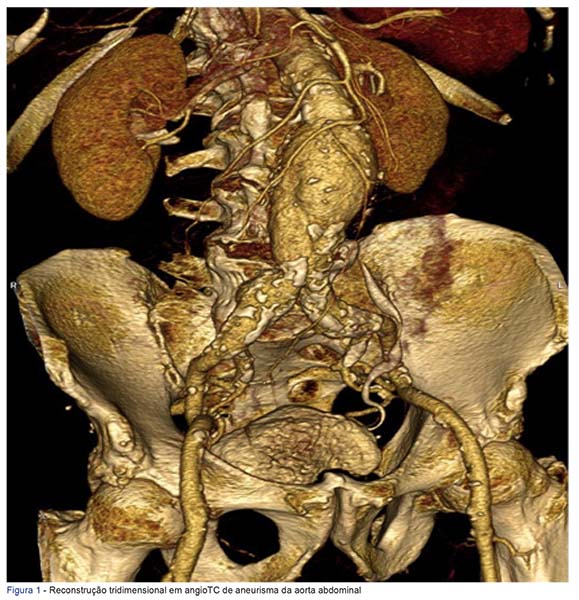

Introduction: To evaluate the results of the abdominal aortic aneurism endovascular treatment (EVAR), percutaneously and with local anesthesia, accord...